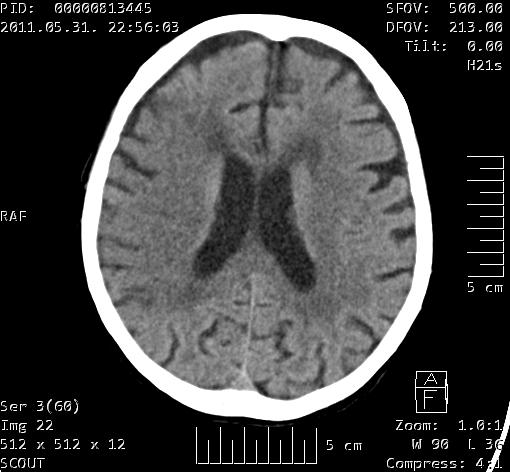

Ischaemiás stroke a jobb oldali a. cerebri media ellátási területén Szerző: admin | júl 6, 2011 | Brain | Nincsenek hozzászólások Az a. cerebri media területén az agyállomány hypodensebb az ellonoldalinál. Az intergyralis sulcusok keskenyebbek, a gyrusok kontúrja elmosott. A szürke és fehérállomány határa elmosott.